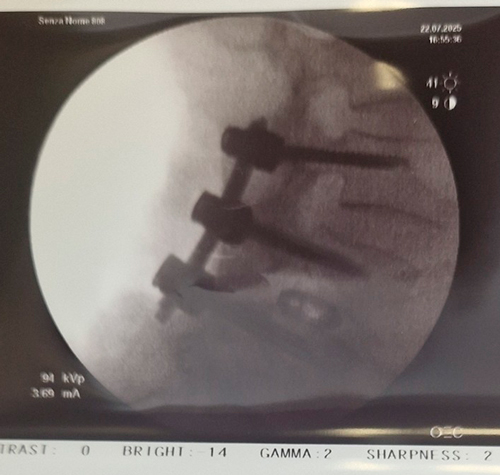

DIAGNOSI:

IPERCIFOSI DORSALE GRAVE

Radiografia dorsale pre operatoria

Intervento chirurgico eseguito:

STABILIZZAZIONE DORSO – LOMBARE CON OSTEOTOMIE CORRETTIVE

Radiografia dorsale post-operatoria